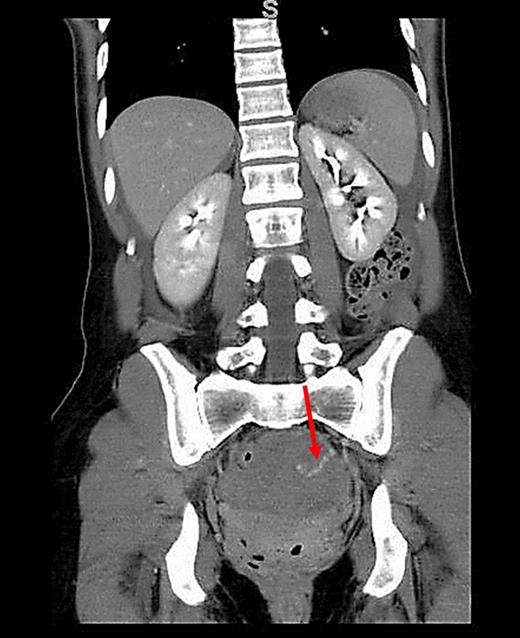

A 34-year-old female with no past medical history was transferred to our emergency department from an outside hospital due to concern for intra-abdominal bleeding. She initially presented with lower abdominal pain immediately following vaginal intercourse described as nonvigorous with the patient mostly ‘on top’, and no history of foreign body use or trauma. CT of the abdomen and pelvis with IV contrast performed at the outside hospital revealed an intra-abdominal hematoma with extravasation of contrast questionably from one of the branches of the left internal iliac artery (Figs 1 and 2). No adnexal lesions were identified on the CT. Upon arrival, the patient was complaining of constant, sharp, severe bilateral lower quadrant abdominal pain, nausea and fatigue. There was no history of loss of consciousness, vomiting, vaginal or rectal bleeding, or hematuria. A past surgical history consisted of appendectomy. Her last menstrual period was 19 days prior to presentation.

CT (axial view) of the pelvis showing extravasation of contrast material into the left pelvis (red arrow).